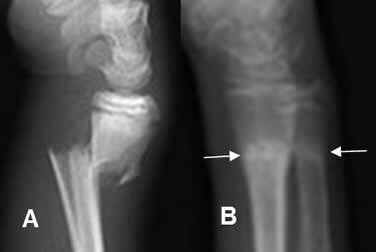

lesiones agudas: (contracturas, elongaciones, lesiones fibrilares y rupturas musculares)

lesiones crónicas: lesiones crónicas o complicaciones como la fibrosis muscular, el nódulo fibroso cicatricial o hematoma enquistado y la miositis calcificante.

complicaciones

Aparecen, como consecuencia de una evolución inadecuada de las lesiones musculares, produciendo unos síntomas dolorosos persistentes. Se describen 3 tipos de complicaciones musculares: la fibrosis muscular, el nódulo fibroso cicatricial y la miositis osificante o miositis calcificante.